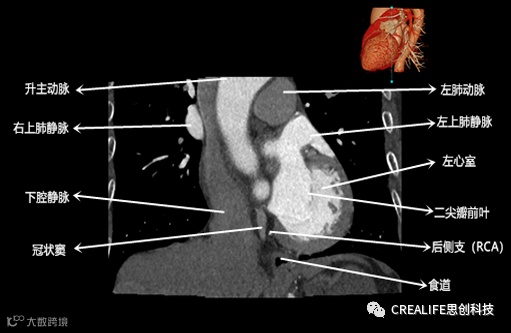

今天,跟大家分享心脏影像的经典层面——冠状位。通过冠状位的影像,我们可以从正位观察到心脏结构,看到主动脉的纵向剖面及冠窦交界处的心脏形态等多方位的心脏结构。现在,就让我们率先一睹“冠状位”的奇妙风采吧!

毋庸置疑,影像解剖学可为医师提供优良的诊断依据,包括瓣膜钙化程度、主动脉瓣环直径、主动脉窦直径及高度、冠状动脉开口高度、入径血管直径等关键数据,以此,为术前提供更全面的评估指标。